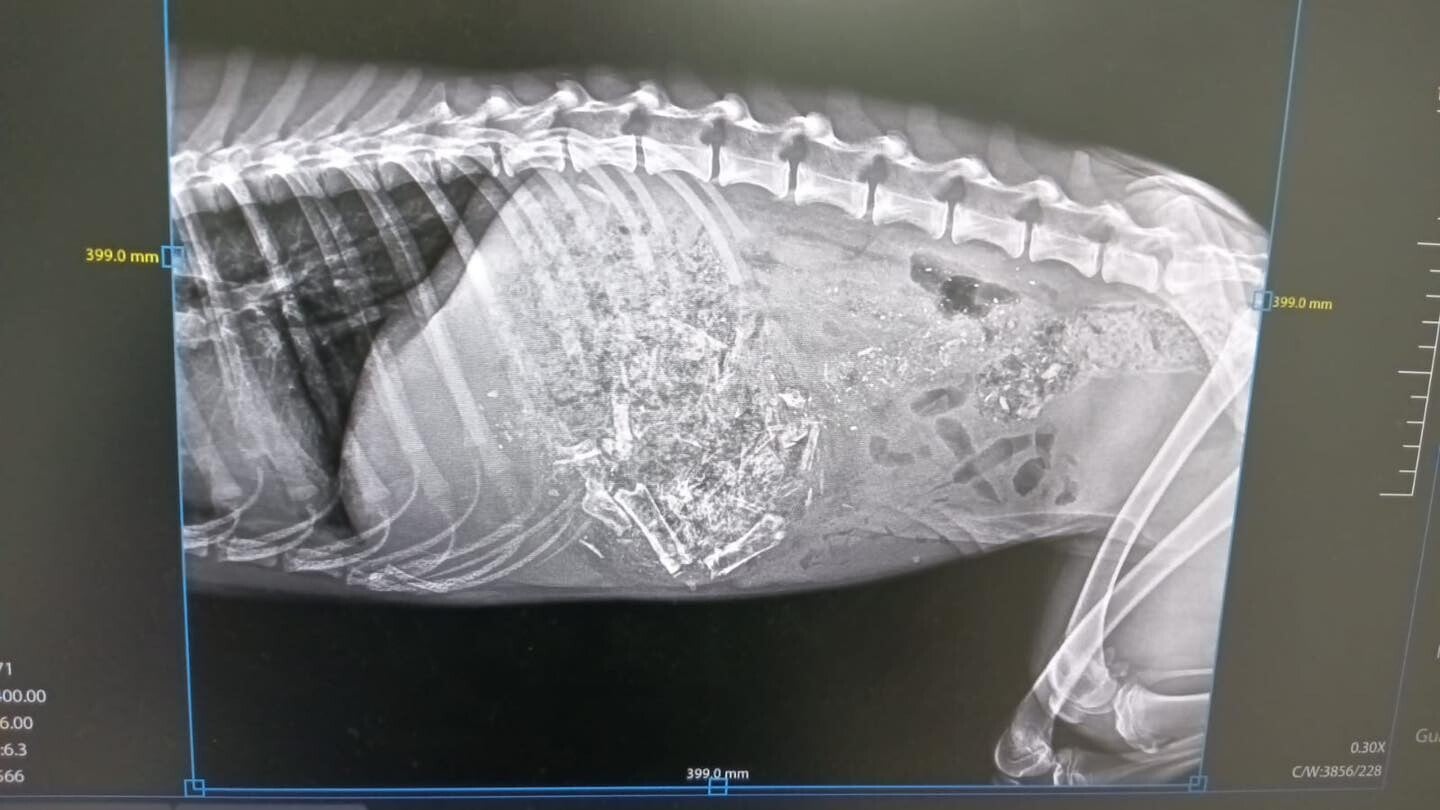

Dit is  Flavia, ze is ongeveer een jaar oud en op brute wijze overreden. Ze heeft twee gebroken benen,  een gebroken opperarmbeen op één van de voorste ledematen, en één van de achter ledematen. de kop van de dijbeen en de heup zijn gebroken en dan heeft ze ook nog een scheur in de maag.